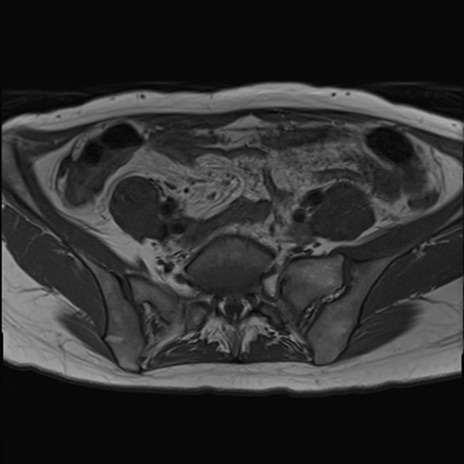

症例39 T1WI(横断像)

MRI(4日後)